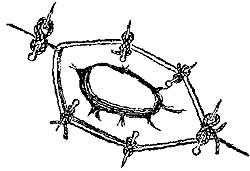

The four plates which precede the letterpress were drawn on wood (from original photographs) by Mr. D.W. Williamson, Melbourne Place, and the lines of incision for the various operations were added by the author.

The rough woodcuts scattered through the work were drawn on wood by the author, and for their roughness he, not his engraver, is responsible. He also hopes that the references in the letterpress will be accepted as sufficient acknowledgment of the true ownership, in those few instances in which the idea of the diagram has been borrowed.

In sewing up the wounds in the abdominal walls, advantage will be gained by putting in a certain number of stitches so deeply as to include the whole thickness of the muscles, and in the intervals between these deep ones to insert others less deeply, so as accurately to approximate the edges of the skin. This will both facilitate union and also render the occurrence of hernia less probable. This latter accident did occur in a case, otherwise successful, in which Mr. Kirby tied the external iliac.